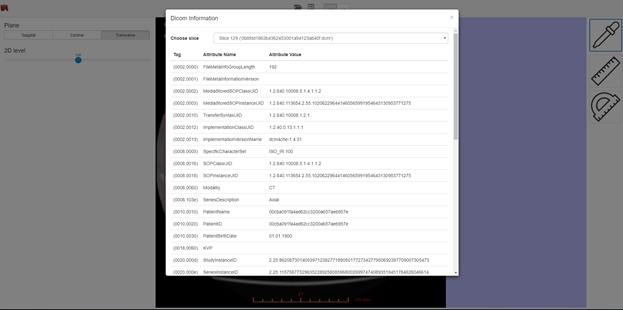

DICOM tags displaying.

The functionality depends on the selected visualization mode (2D or 3D), and in case of 3D mode on the selected visualization method. The screenshot below shows a 3D visualization mode with a volume render method. In this case, the interface provides the ability to select areas of interest inside the volume, brightness and contrast adjustment, as well as the ability to use the near clipping plane position.